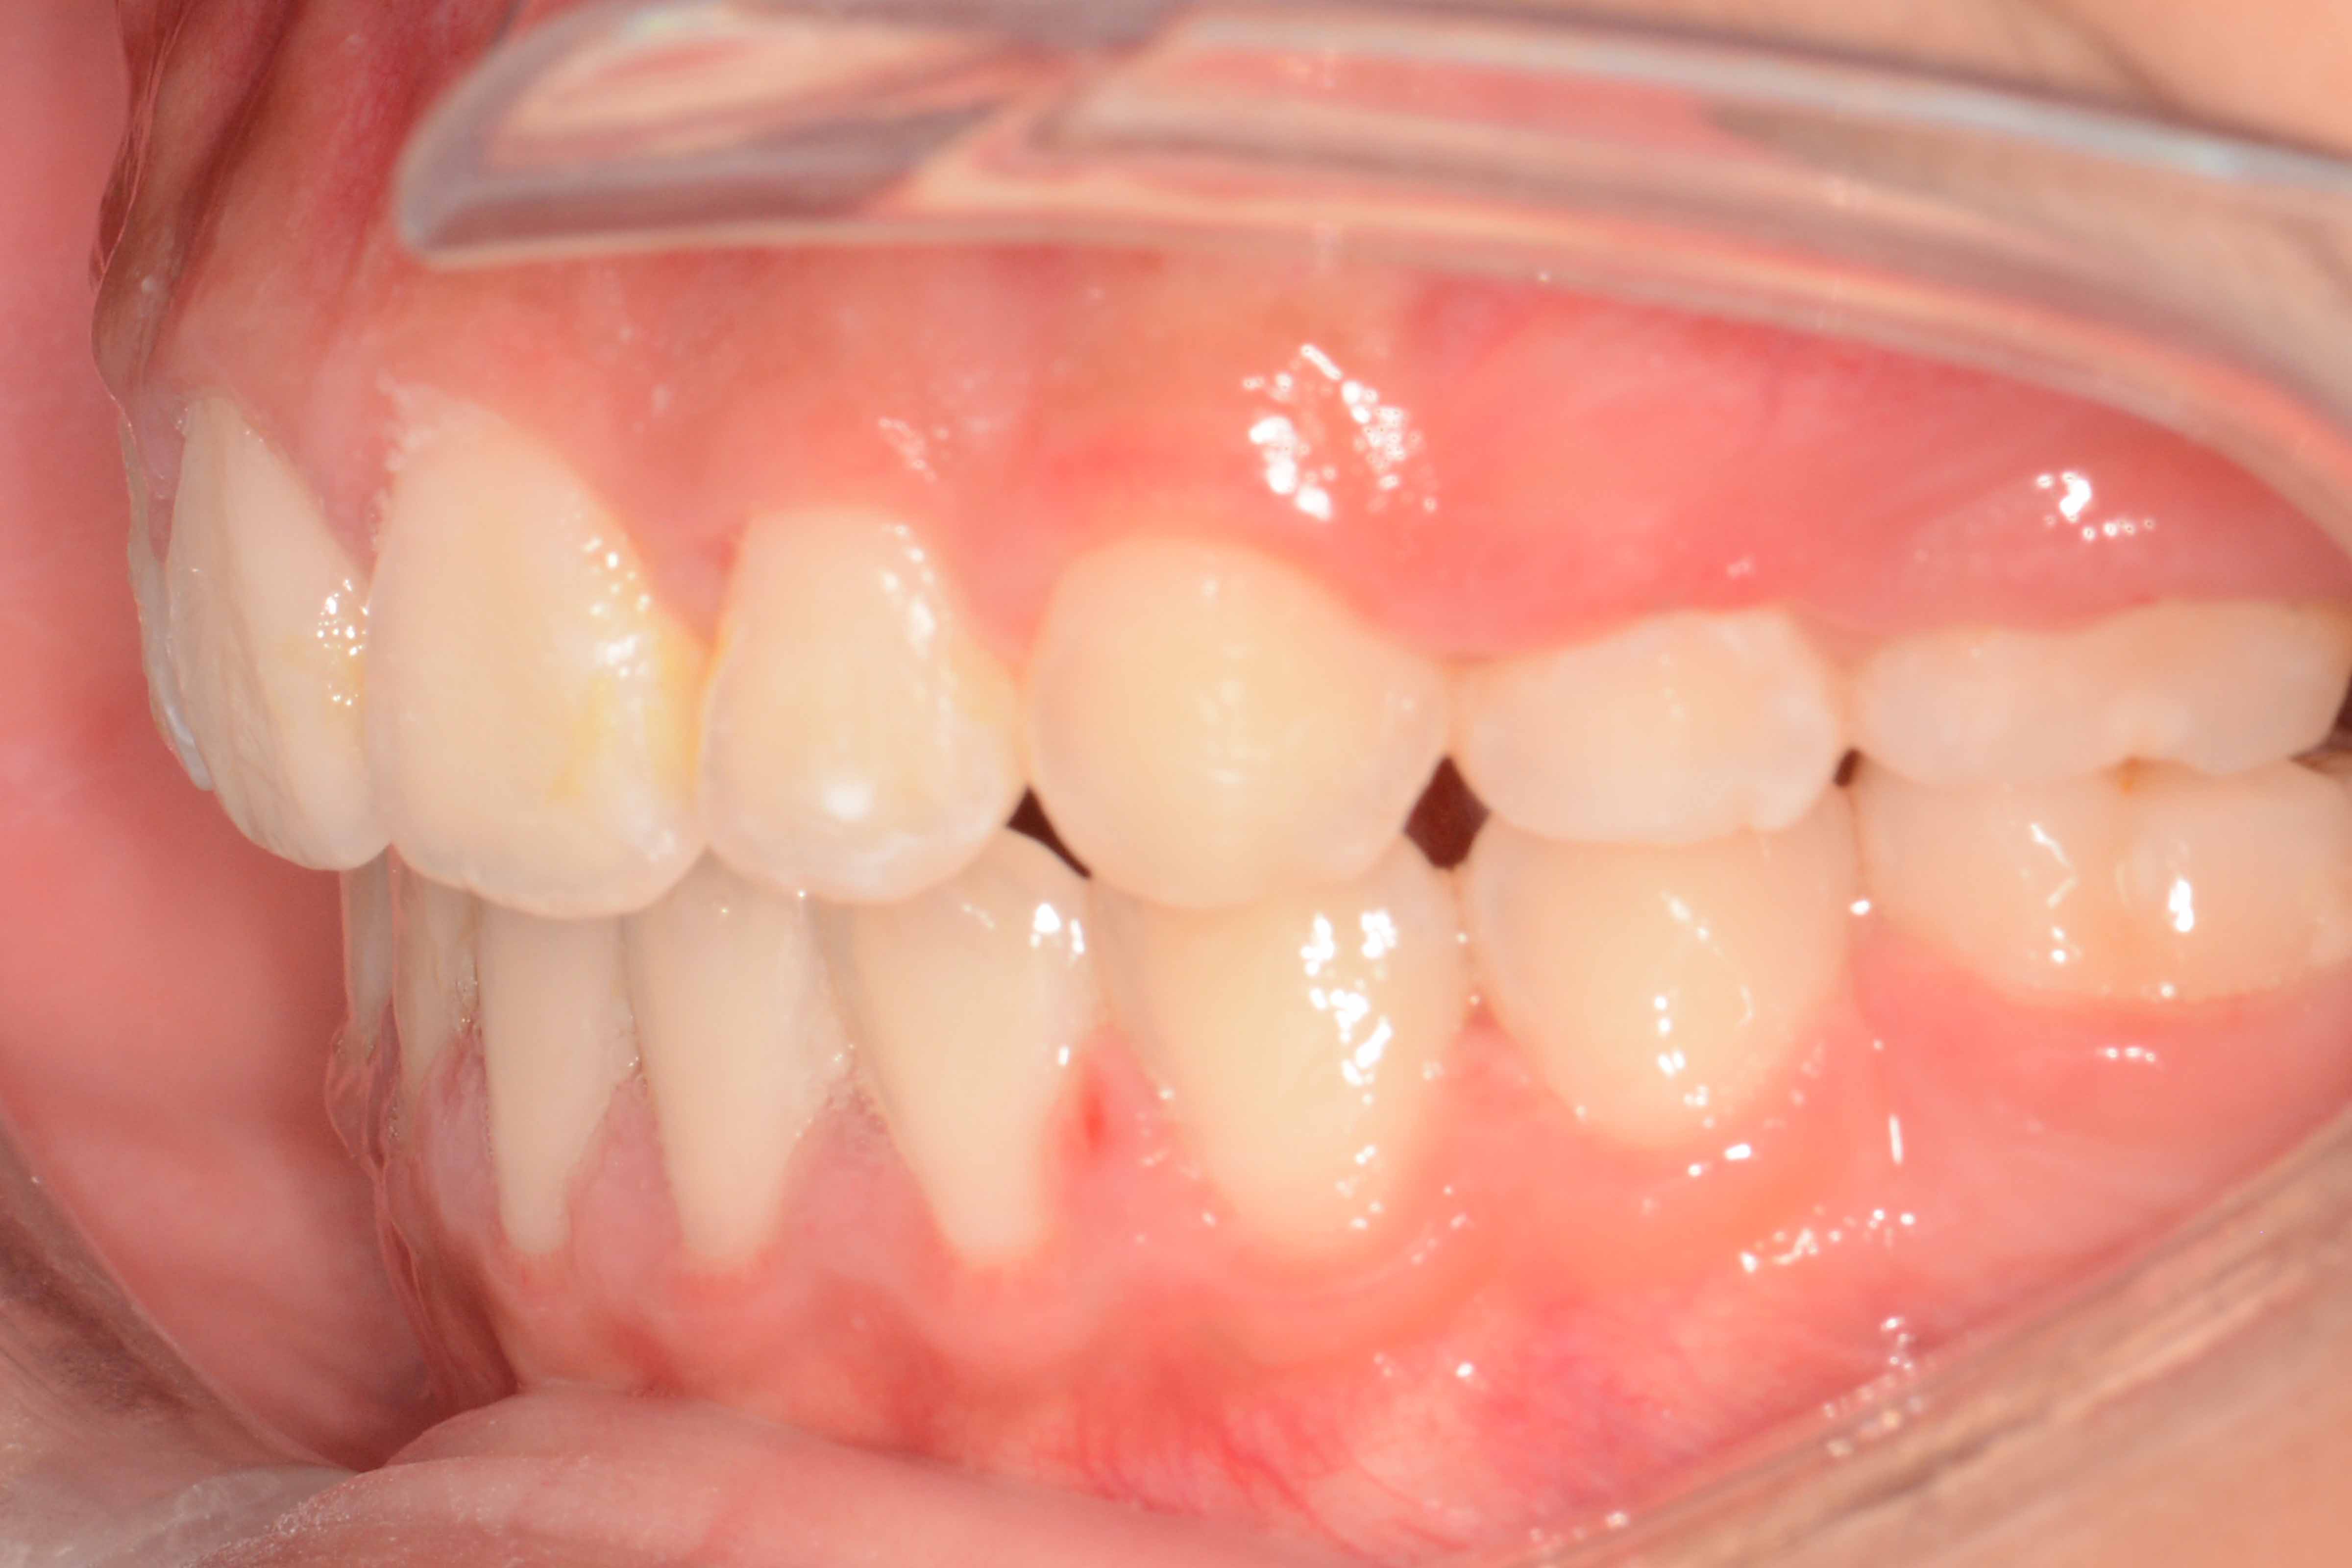

患者:14岁女性

主诉:前牙咬不住,进食不便

前牙区开颌3mm

诊断:安氏II类错颌畸形  开颌

矫治前: